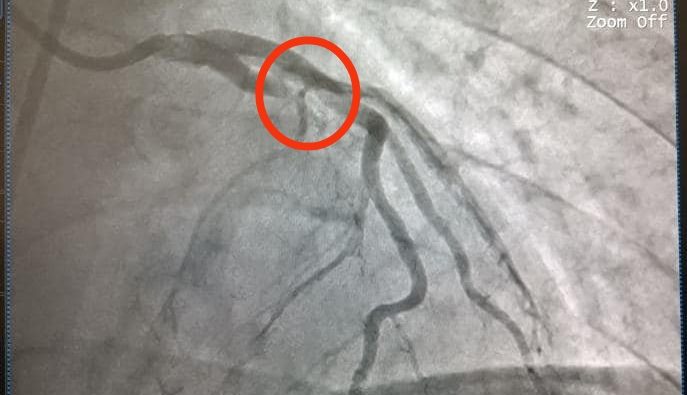

Do có sự chuẩn bị và phối hợp từ trước, bệnh nhân nhanh chóng được chuyển thẳng về Đơn vị Can thiệp mạch để chụp động mạch vành, kết quả là tổn thương tắc hoàn toàn động mạch liên thất trước, huyết khối lấp đầy động mạch. Sau 20 phút căng thẳng, ê kíp các bác sĩ đã hồi sức cấp cứu và can thiệp thành công, lấy huyết khối, đặt stent tái thông động mạch cứu sống bệnh nhân.

Hình ảnh chụp động mạch vành của bệnh nhân sau can thiệp